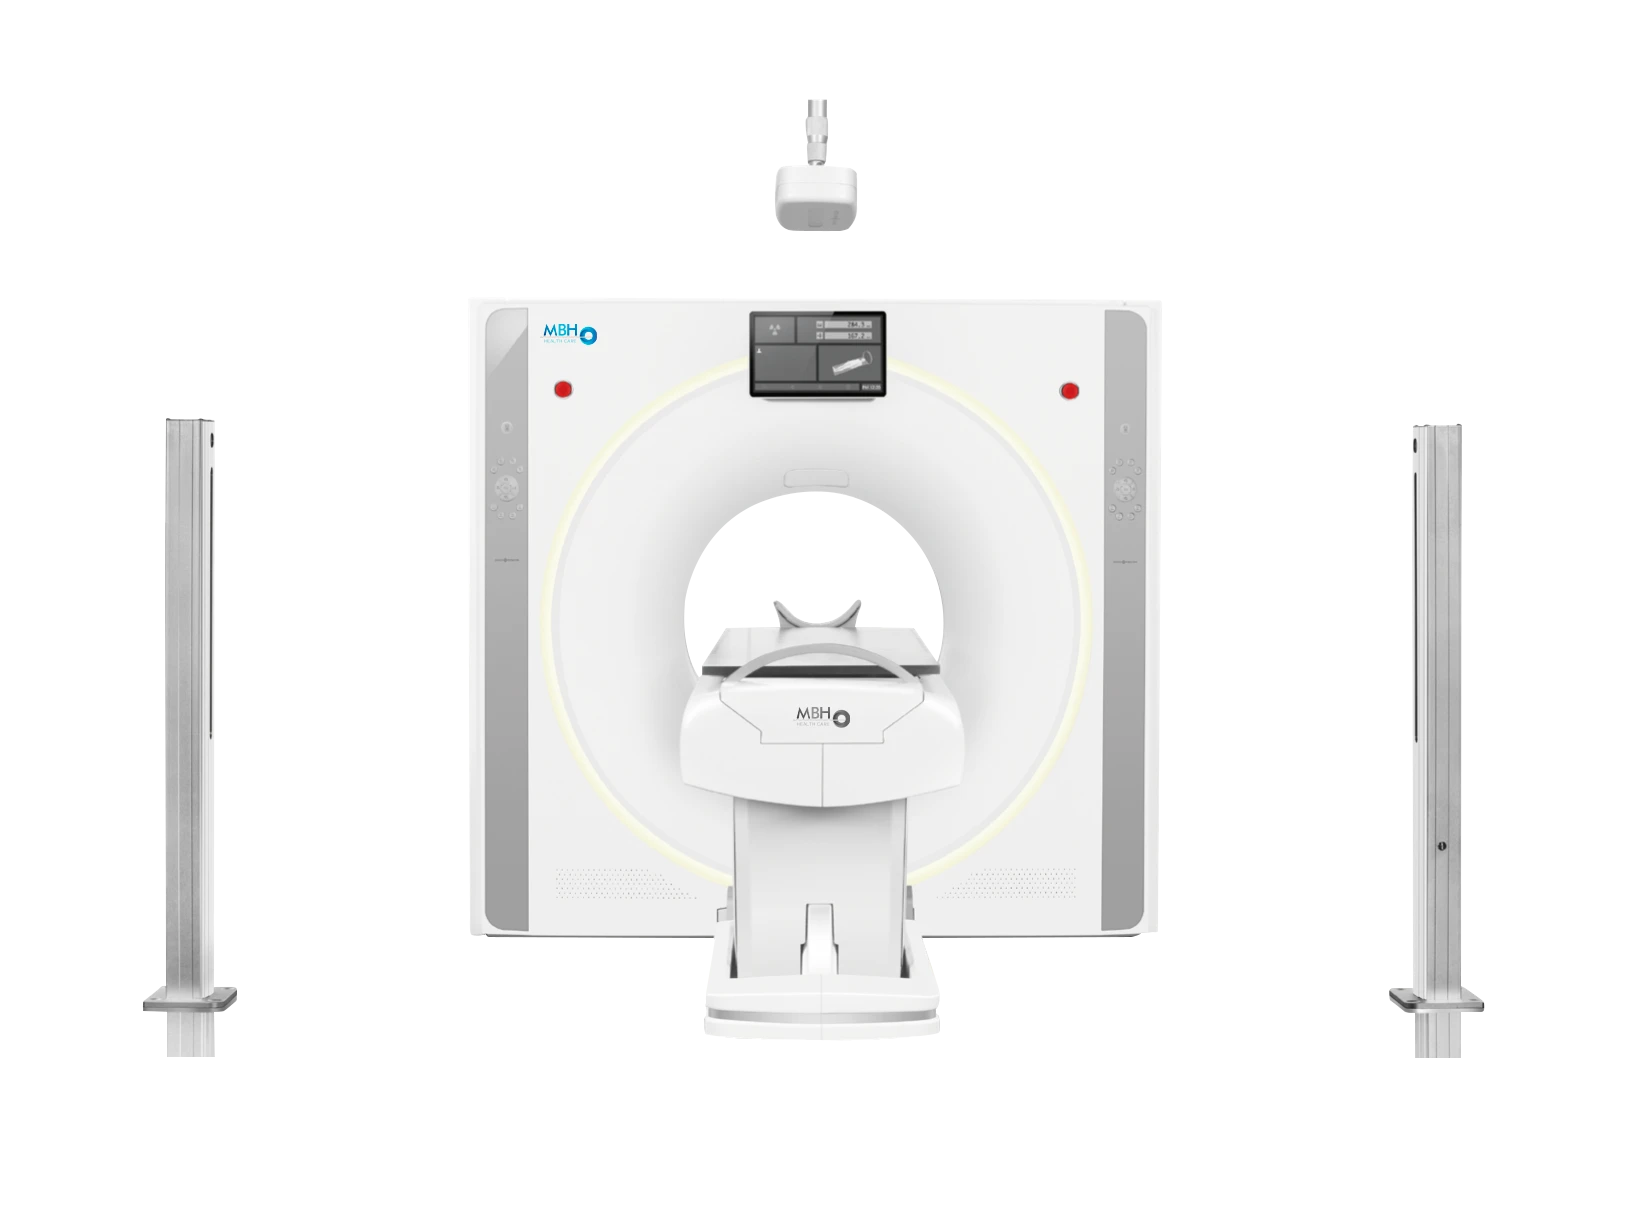

Tomograph

MBH-60

• Intelligenter 64-Zeilen-CT-Scanner mit großem Durchmesser.

- – Öffnung: 75 cm